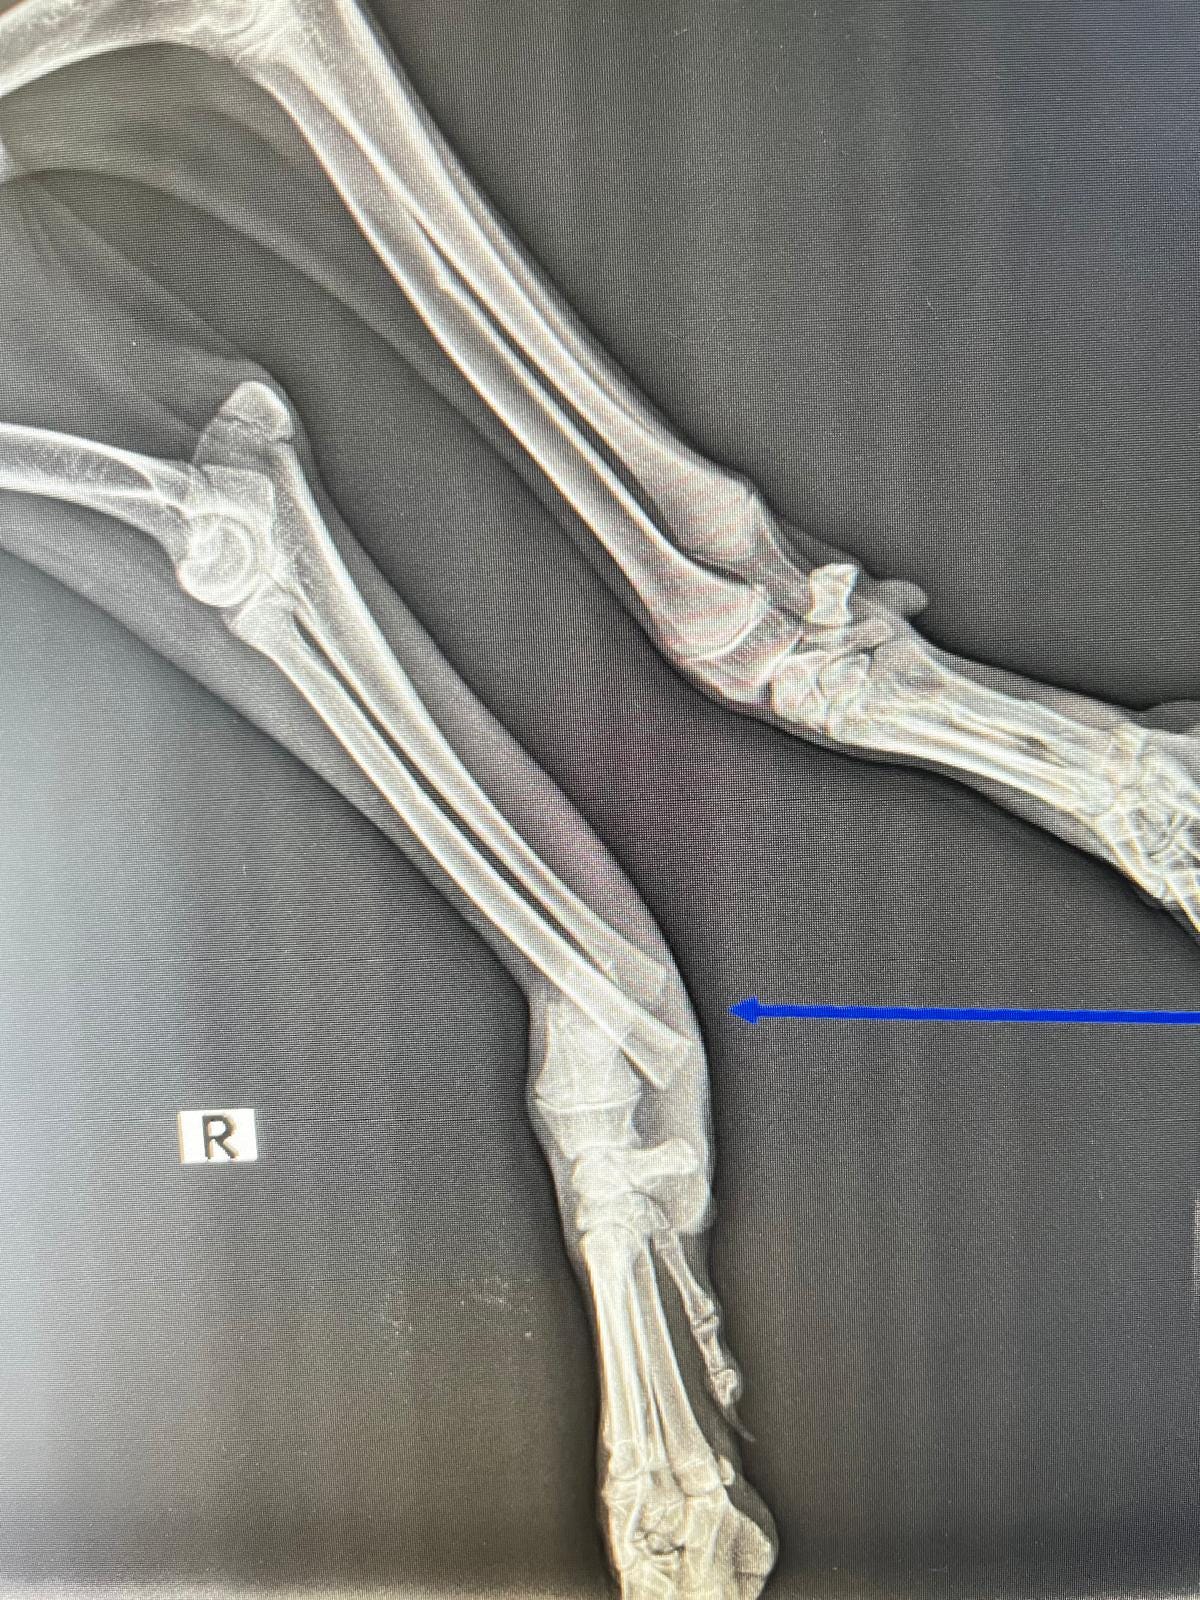

As you can see from the x-rays poor Patch had multiple breaks affecting three of his legs. He must have been in such a great amount of pain & so stressed.

He underwent several surgeries to repair the breaks with the use of plates & he also needed an external fixator.